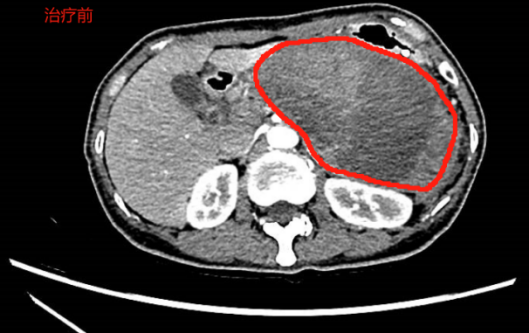

手术过程流畅,即刻见大量坏死液顺利引流。术后第三天,CT复查结果令人振奋,坏死包裹从13厘米显著缩小至9厘米,胃部压迫得到有效缓解。

红色为坏死性包裹,蓝色箭头为支架